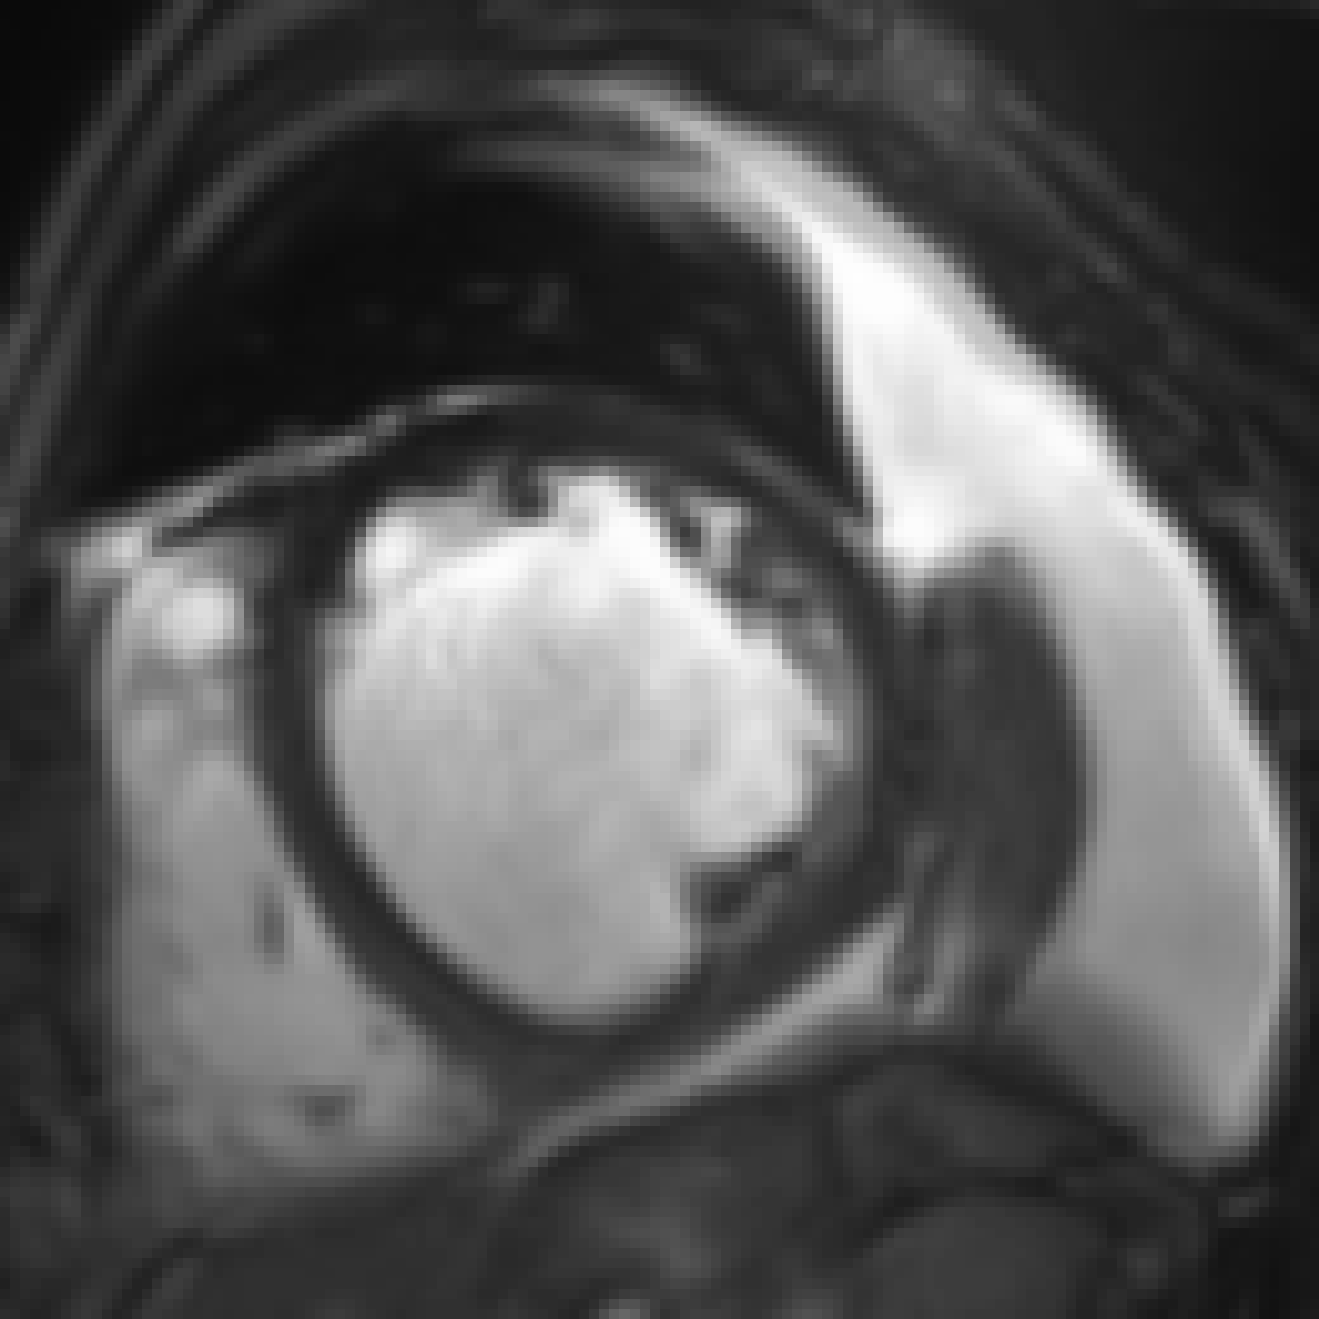

Figure 5: Qualitative evaluation of image synthesis performance of proposed method on cardiac cine MRI (ACDC dataset). Slice spacing was improved from 101010 to 1.43 mmtimes1.43millimeter1.43\text{\,}\mathrm{mm} by synthesizing six intermediate slices (second to penultimate columns) using latent space encodings of the two neighboring slices (first and last column). α𝛼\alpha denotes the mixing coefficient as specified in Equation 1.

Slice Synthesis: Qualitative evaluation of synthesis performance of the proposed method conveys that synthesized slices, i.e. those that are generated using a convex combination of the neighboring slice encodings, show an anatomically and semantically meaningful transition between the two neighboring slices. Moreover, despite large anatomical variations between the neighboring slices for the right ventricle, left ventricle and trabecular structures of the left ventricle, the proposed method can generate slices that depict an anatomically smooth transition between the neighboring slices. Figure 5 illustrates three example evaluations for basal, mid-ventricular and apical MRI slices, respectively, where upsampling factor K𝐾K was set to 777 and 𝒜𝒜\mathcal{A}, the set of mixing coefficients was equal to {1/7,2/7,3/7,4/7,5/7,6/7}172737475767\{\nicefrac{{1}}{{7}},\nicefrac{{2}}{{7}},\nicefrac{{3}}{{7}},\nicefrac{{4}}{{7}},\nicefrac{{5}}{{7}},\nicefrac{{6}}{{7}}\}. Furthermore, quantitative evaluation of synthesis performance assessed on downsampled cardiac cine MRI scans listed in Table I reveals that synthesis performance is lower than reconstruction performance.